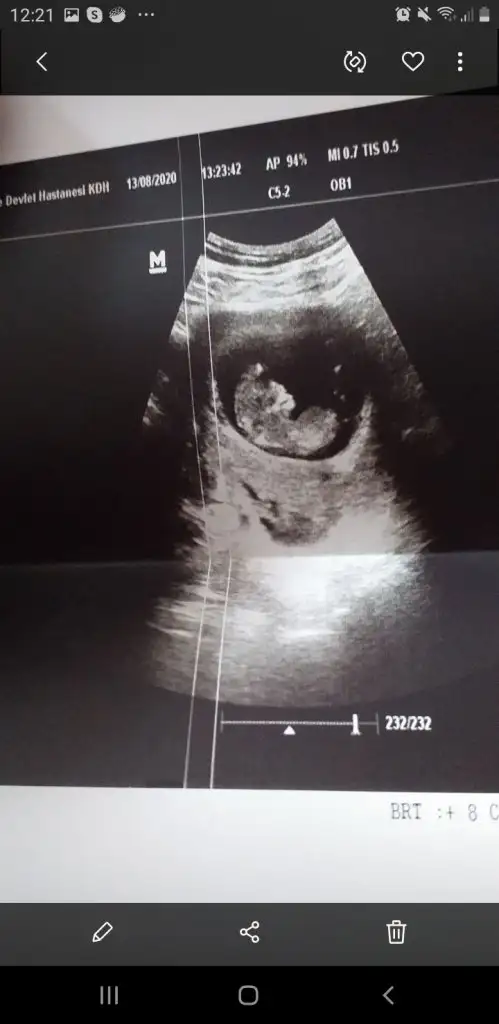

Banada tahmin yürütün

• 78B3FD87-3824-48F6-BD06-424FCEB5E299.webp

78B3FD87-3824-48F6-BD06-424FCEB5E299.webp

27 KB · Görüntüleme: 119